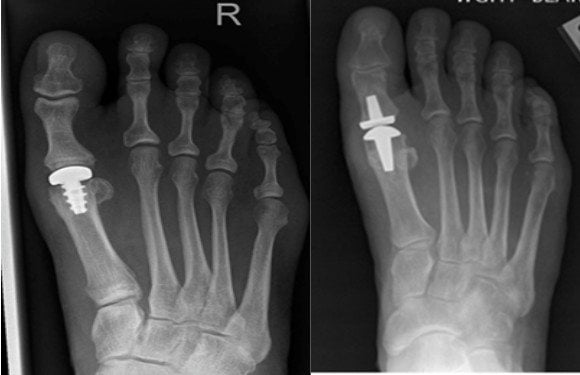

Сегодня в клиническую практику постепенно внедряется метод тотального эндопротезирования I плюсне-фалангового сустава стопы. Подобное лечение проводится при остеоартрозе, который сопровождается выраженным болевым синдромом. Во время операции врачи полностью удаляют разрушенный сустав и заменяют его искусственным протезом.